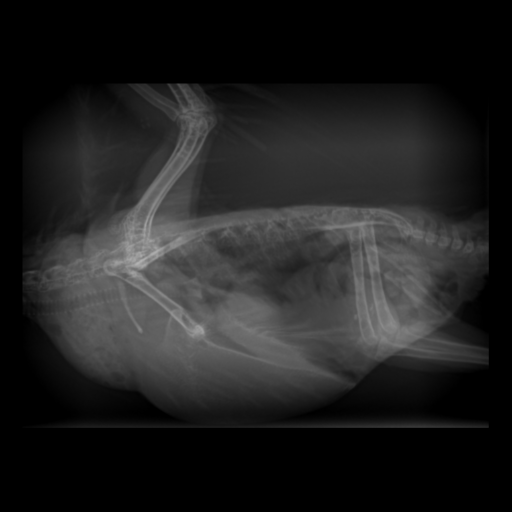

○レントゲン検査

視診・触診では見えない体の中の状態をチェックします。

- 骨・関節

- 呼吸器(肺、気管、気嚢)

- 消化器(そのう、食道、胃腸、クロアカ)

- 肝臓

- 心臓・血管

- 腎臓

- 生殖器(精巣、卵巣、卵管)

- 脾臓

造影検査